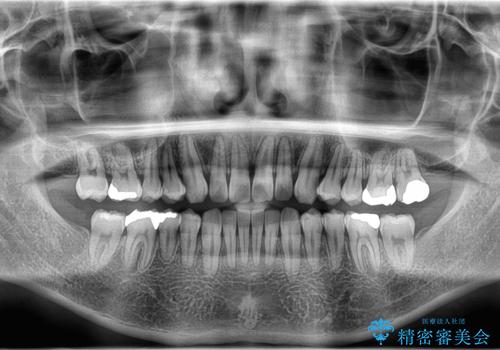

- 前歯の隙間と歯のデコボコを主訴にご来院された患者様です。

加えて、上下の奥歯が全く咬み合わないシザーズバイトの状態も認められました。

矯正検査の結果、非抜歯でインビザラインによる治療が可能と判断し、治療を行いました。

歯の隙間とデコボコ、シザーズバイトも改善され、咬み合わせや見た目が整い、患者様にも大変ご満足いただけました。